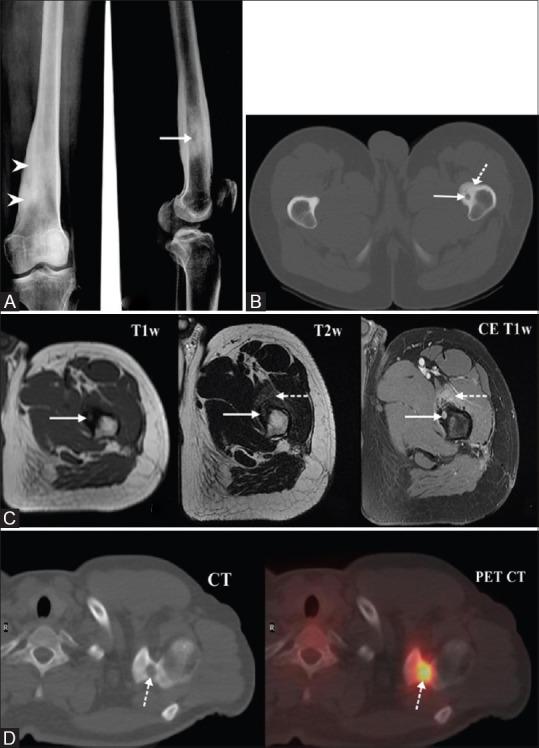

MATERIALS AND METHODS

This is a retrospective analysis of prospectively maintained data of 43 symptomatic osteoid osteoma patients who were treated by radiofrequency ablation (RFA). Forty out of 43 patients were naive cases and underwent primary treatment for osteoid osteoma with RFA, whereas 3 patients included in the study underwent RFA for local recurrence after having undergone surgical treatment. Diagnosis was based on clinical and characteristic imaging findings, and biopsy was done for cases with atypical presentation. Pre and post procedure Visual Analog Score (VAS) was documented in all cases. Monopolar RFA system was used in all patients, and the electrode was placed within the lesion nidus under CT guidance coaxially through 11G introducer needle. Ablation was performed at 90° C for 5 min.

RESULTS

Technical success rate of intranidal placement of electrode was 100%. The primary clinical success in our study was 97.7% (42 of 43), and the secondary clinical success was 100%. Pre and postprocedure VAS score in our study group was 7.8 and 0.4, respectively. Mean follow-up period in our study was 48 months (Range: 4-129 months). One patient had recurrence of pain 4 years after treatment and was treated successfully by a second session. Minor complications were seen in 3 patients with two cases of RF pad burns and one case of skin burn at the treatment site, and these were managed conservatively. No patients developed temporary/permanent neurological deficits, and no procedure-related mortality was seen in our study.

材料与方法

这是一项对43例接受射频消融(RFA)治疗的有症状骨样骨瘤患者的前瞻性维护数据进行的回顾性分析。43例患者中有40例为初发病例,接受了RFA治疗骨样骨瘤的初次治疗,而纳入研究的3例患者在接受手术治疗后因局部复发接受了RFA治疗。诊断基于临床和特征性影像学表现,对于表现不典型的病例进行了活检。所有病例均记录了术前和术后视觉模拟评分(VAS)。所有患者均使用单极RFA系统,电极在CT引导下通过11G穿刺针同轴放置在病变巢内。在90°C下进行5分钟的消融。

结果

电极巢内放置的技术成功率为100%。我们研究中的主要临床成功率为97.7%(43例中的42例),次要临床成功率为100%。我们研究组术前和术后VAS评分分别为7.8和0.4。我们研究的平均随访期为48个月(范围:4 - 129个月)。1例患者在治疗4年后疼痛复发,通过第二次治疗成功治愈。3例患者出现轻微并发症,2例为射频垫烧伤,1例为治疗部位皮肤烧伤,均经保守处理。我们的研究中没有患者出现临时/永久性神经功能缺损,也没有观察到与手术相关的死亡。